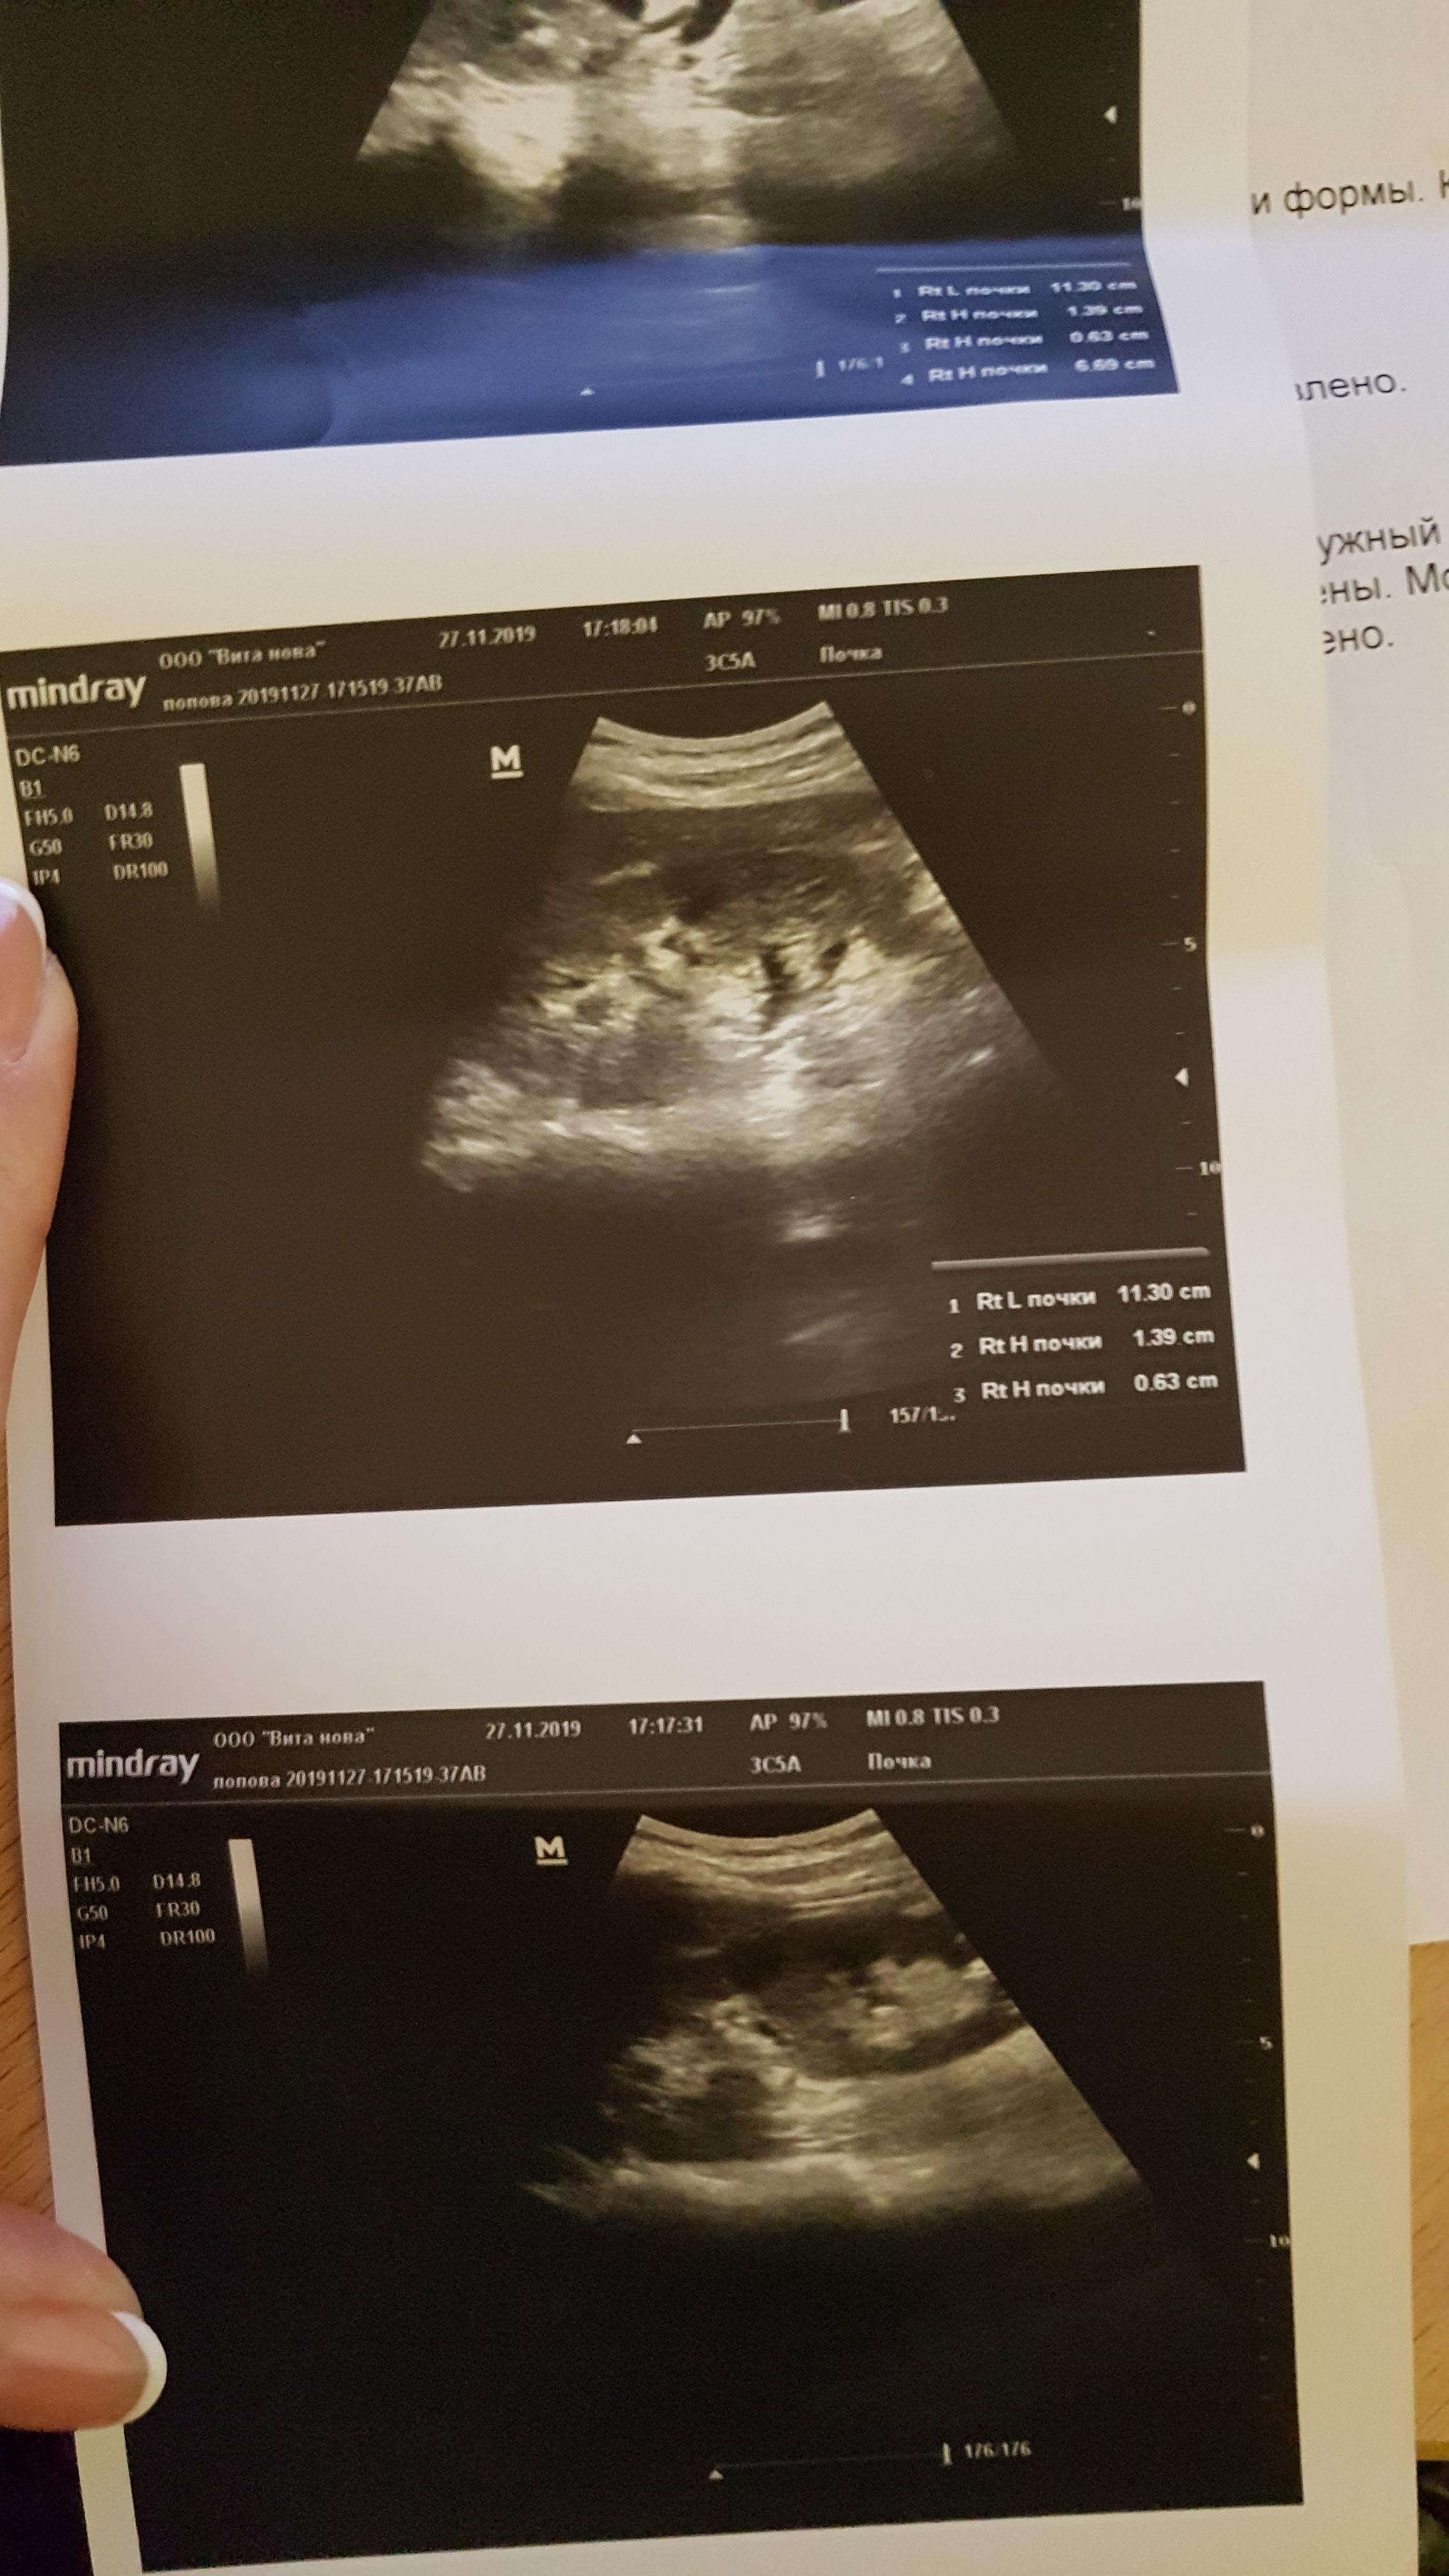

Добрый вечер! Недавно у меня заболела поясница слева. Обратилась к терапевту. Она назначила общий анализ мочи и пропить милдокалм, мелоксикам. Анализ пришел в норме. Мне сказали, что это остеохондроз. Я решила сделать узи почек и мочевого пузыря. Вот заключение: гидронефротическая трансформация левой почки, уз-признаки хр. пиелонефрита левой почки. Скажите, пожалуйста, что то надо с этим делать? Спасибо!

Здравствуйте! Надо сделать МСКТ(мультиспиральную компьютерную томографию ) почек и мочеточников для уточнения уродинамики верхних мочевых путей. С результатом обратитесь к урологу очно. Удачи!